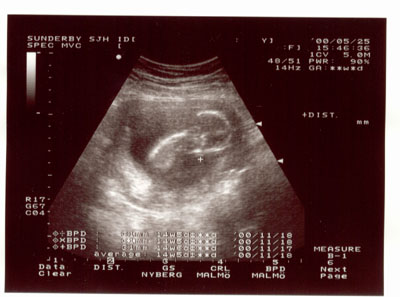

E.T. är 3 månader nu. Har armar och ben men kan ännu inte höra.

Jag tror att vid krysset syns E.T´s arm som kliar näsan. Ovanför den vita armen kommer det stora runda huvudet med ansiktet nedåt.Ryggraden syns som ett böjt vitt streck till vänster.

I think it´s the arm at the white cross. Above it you can see the big head.